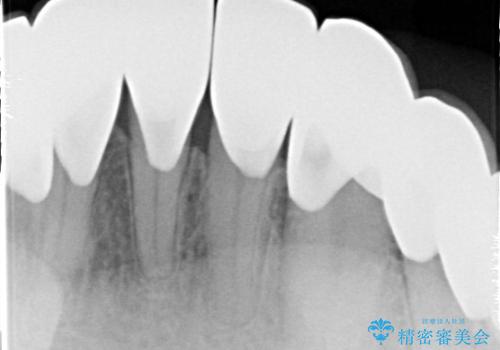

- 昔、他院で治療したダイレクトボンディング(歯の表面にだけ白い材料を盛る治療)のやりかえを主訴に来院されました。叢生の改善も同時に行うためにオールセラミッククラウンにより治療を行いました。

再治療を避けるため、適合精度にこだわり治療を行なっております。

ダイレクトボンディングでの治療より、天然歯に近い見た目を再現することができます。